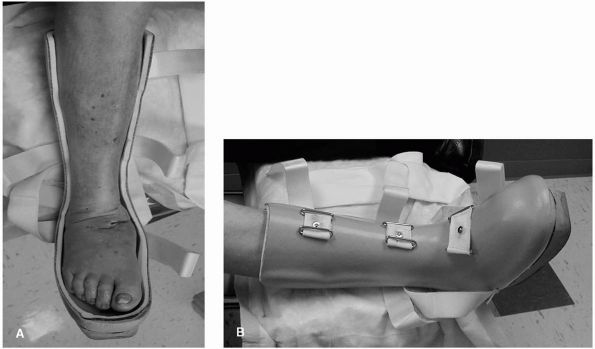

![]() |

FIGURE 21-26. An ankle-foot orthosis may be used with and without an anterior shell to help contain the foot and ankle.